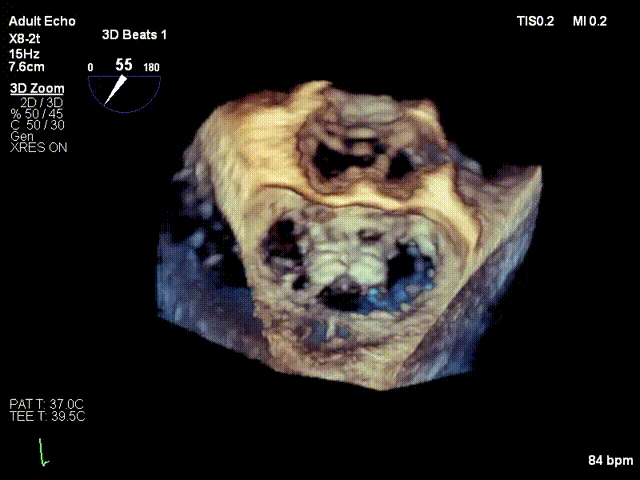

术前3D

前后瓣叶均可见栓系

反流主要来源于2区累及1、3区